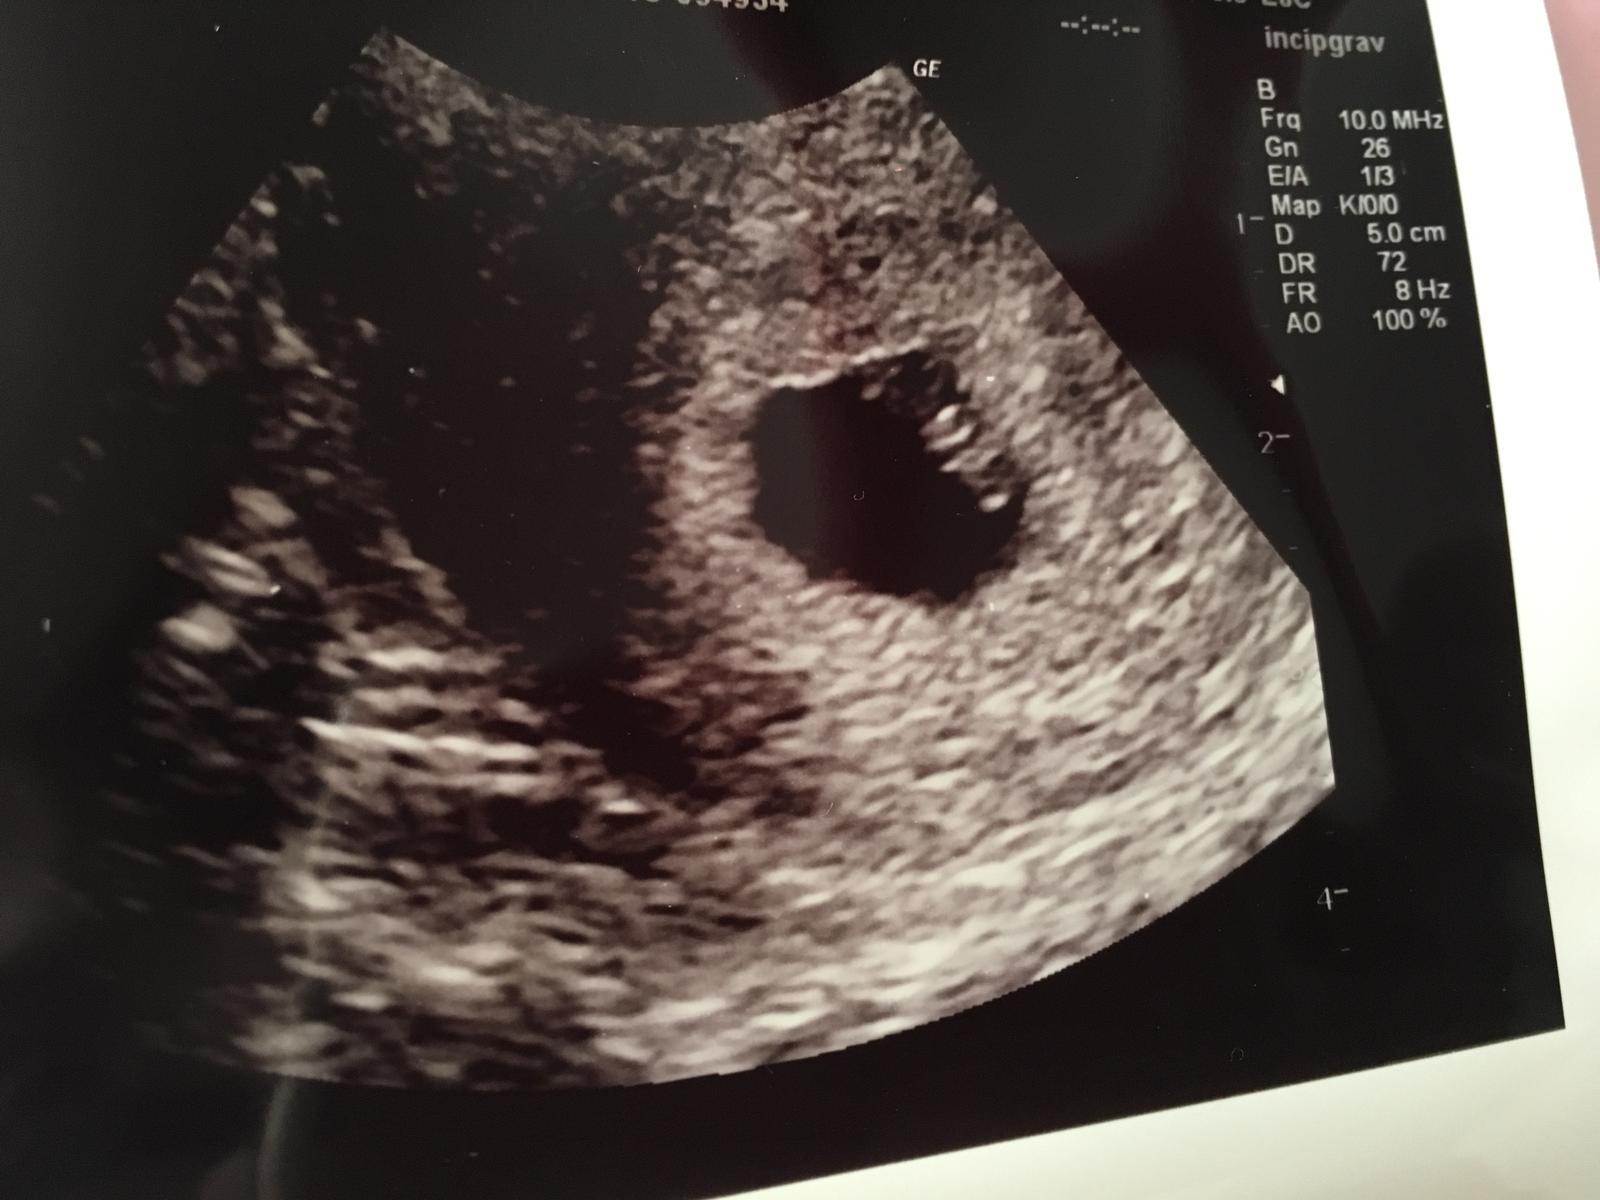

Ahoj holky, tak se hlásím 🙂 srdíčko bylo!🙂 prcek je tam kde má být, podle utz o týden mladší než podle MS. Mám velikánskou radost, už teď vím, že to je bojovník nebo bojovnice 🙂 🙂)) a všem ostatním hodně štěstí a držím palce, ať jsou na testu //. :-*

@miky00 ahojky tak to je paráda že aspoň jedno 🙂 no mi jsme dnes 7+0 takže to máme skoro stejně už máme i fotečku,malá houstička se srdíčkem taky doufám že budeme růst tak jak máme 🙂 tak držíme palečky 🙂 jen mi zatim nepřijde že bych byla těhotná,žádný příznaky kromě hladu a bolesti prsou :D

Ahojky všem zítra jdu na potvrzení těhotenství a chtěla bych se zeptat jaký Vám gynekolog dělat první ultrazvuk? Sestřička mi říkala ze mám dorazit a plným nocovym mechyrem takže asi přes bricho mi bude dělat ...